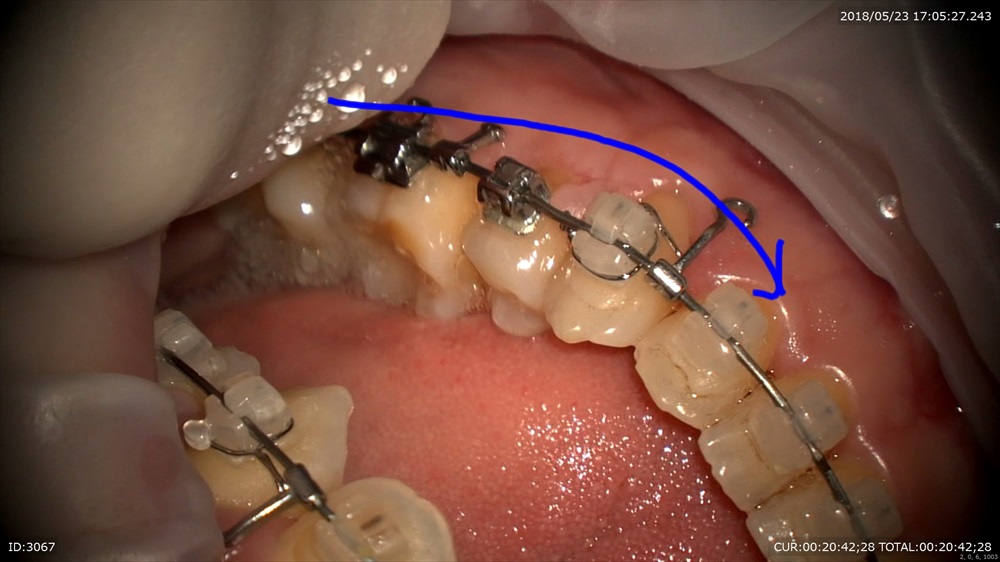

今日のケース。前歯のリトラクションが終了。その反作用でかみ合わせが若干深くなっています。

湾曲がこんな感じ。

マイクロスコープで観察することでトルクの入れ具合が顕著に解る!!